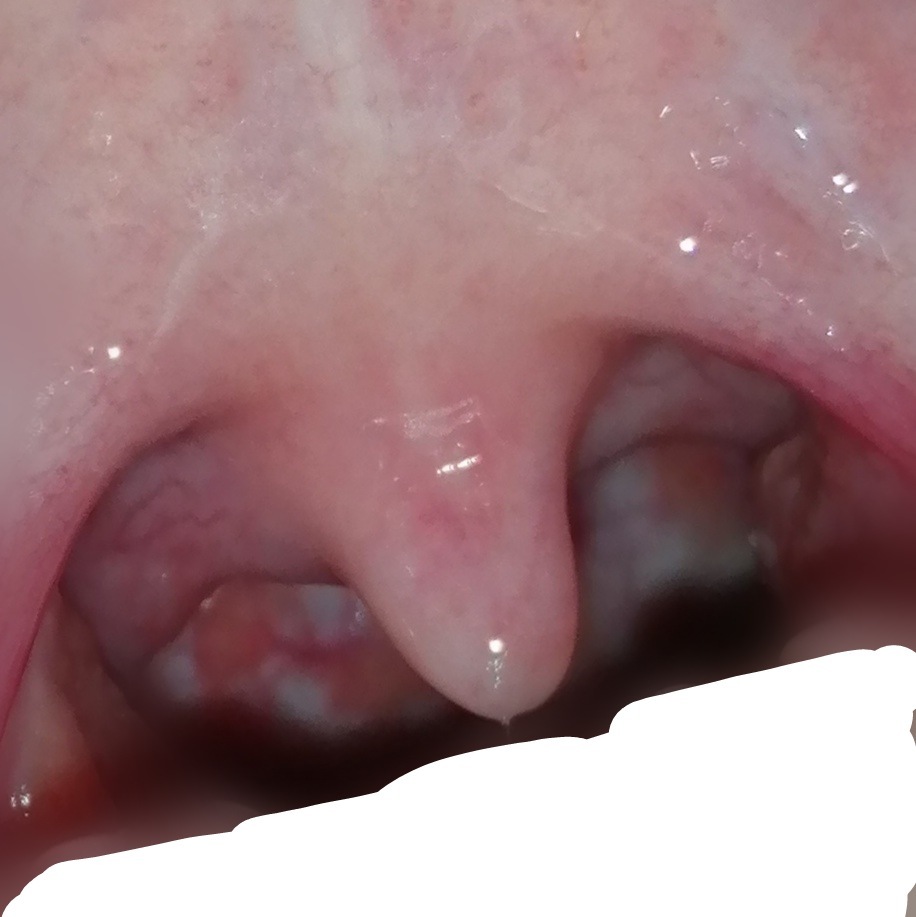

汚い写真ですみません。喉の奥に白いできものが一ヶ月ほど前から... Yahoo!知恵袋

汚い写真ですみません。喉の奥に白いできものが一ヶ月ほど前から... Yahoo!知恵袋 from detail.chiebukuro.yahoo.co.jp

【写真】喉に黒い点。 喉がヒリヒリして痛い。 原因は? 28 pv 📑 体の痛み 肘と膝の皮膚がヒリヒリして痛い 外傷なしでも痛い原因は神経痛? 17783 pv 【写真】腕,脇腹,太も. 喉のロイヤリティフリーのイラスト/ベクター画像が8,086点利用可能です。 首 や 飲む で検索すれば、さらに多くの本格画像が見つかります。 最新順 首 飲む 風邪 舌圧子 目 口 驚き 風.